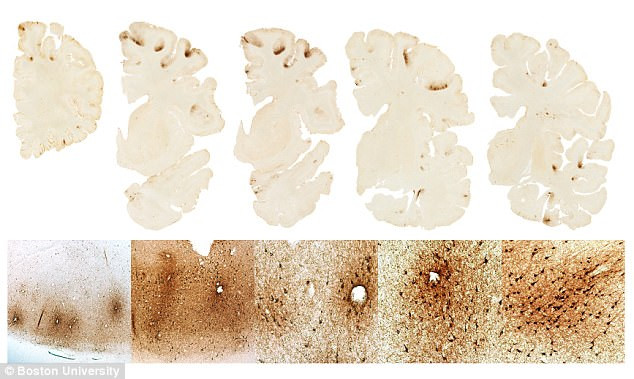

Phát hiện loại protein hỗ trợ chẩn đoán bệnh gây hại não mãn tính ảnh 1Các lớp cắt mô não. (Nguồn: dailymail.co.uk)

Nghiên cứu này đã phát hiện được sự gia tăng mật độ protein CCLL11 trong não bộ của những cầu thủ bóng đá bị mắc CTE đã chết, nhưng không tìm thấy nó ở trong não bộ của những người khỏe mạnh hoặc người bị bệnh Alzheimer.